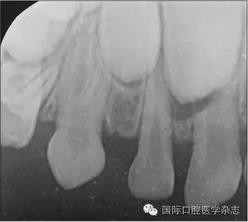

根尖X線片檢查偶然發(fā)現(xiàn):左側(cè)上頜乳尖牙呈雙根,髓腔寬大,牙根自接近根中1/3起至根尖分為明顯的近中及遠(yuǎn)中2個牙根(圖2)?;純杭议L知情同意后,拍攝其他3張乳尖牙根尖片,以觀察牙根是否有異常。X線片示:右側(cè)上頜乳尖牙呈雙根,且形態(tài)、大小及根分叉位置與左側(cè)相似(圖3)。雙側(cè)下頜乳尖牙的形態(tài)及牙根未見異常。詢問病史了解到,患兒體健,足月順產(chǎn),其母妊娠期間無感染或服藥史,患兒嬰幼兒期無外傷史,無兄弟姐妹。

圖2 左側(cè)上頜乳尖牙X線片

Fig 2 Maxillary leftprimary canine radiograph